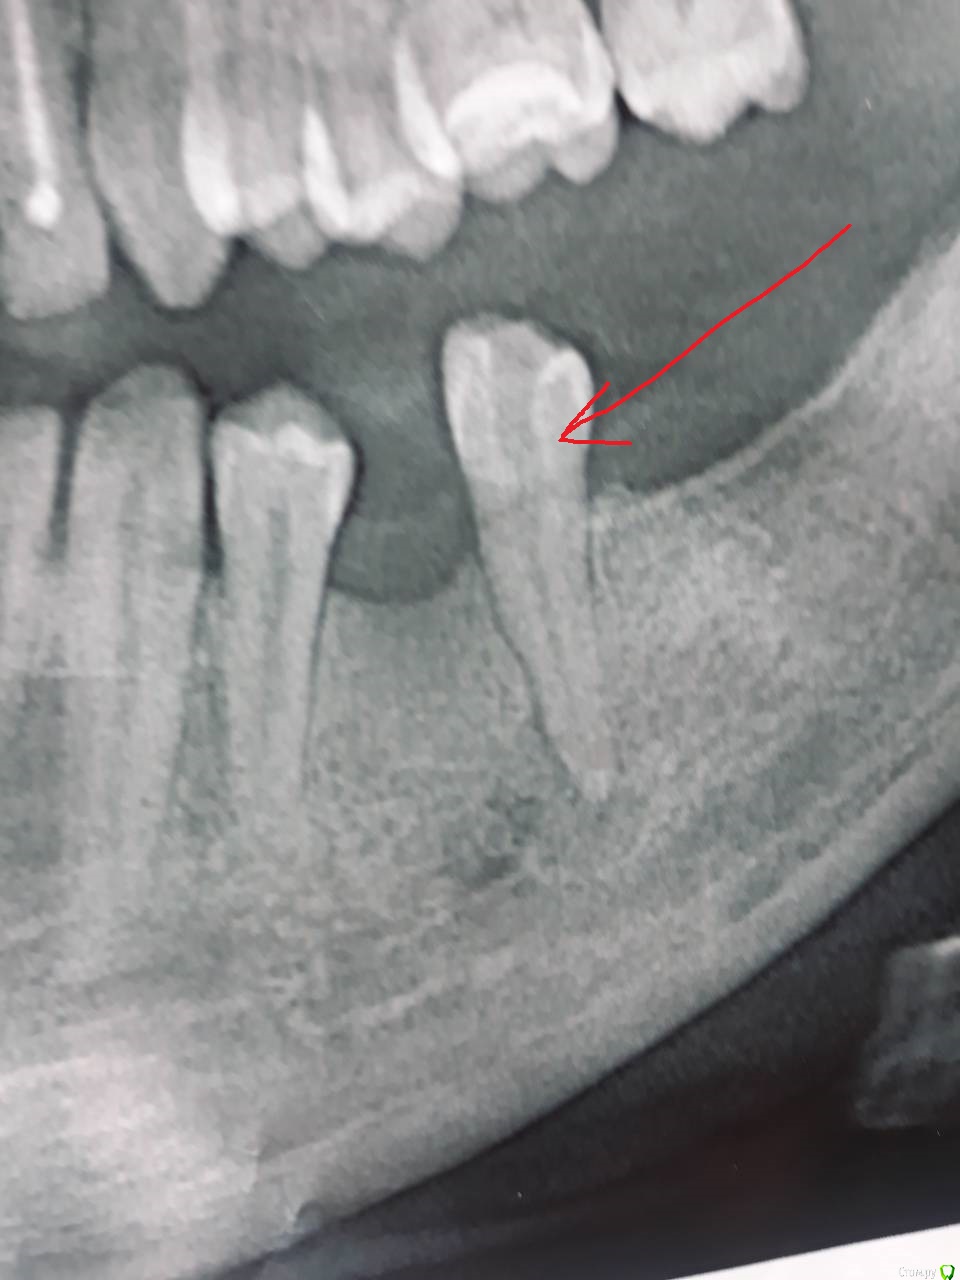

DimaBLR Опубликовано 16 июля, 2018 Поделиться Опубликовано 16 июля, 2018 (изменено) Уважаемые врачи ! Дайте пожалуйста своё мнение, что же на этом снимке ! Мнения наших местных стоматологов разошлось, но я уже не могу, зуб сильно ноет. Канал вскрыли, прочистили, нерв сказали умер, но зуб внешне здоров. Он болит и толком никто не знает что на снимке, или гнойник или что-то там (не помню как точно выразился один стоматолог). При нажатии на щёку со стороны зуба - тоже больно, хотя внешне щека вроде не опухла, но немного онимела Больной зуб показал стрелкой Изменено 16 июля, 2018 пользователем DimaBLR Ссылка на комментарий

St. Опубликовано 16 июля, 2018 Поделиться Опубликовано 16 июля, 2018 Добрый день. За пределами зуба присутствует очаг хронического воспаления (темная область у кончика корня) и нерв действительно умер. Причины возникновения могут быть разными.То что каналы "почистили" это хорошо. Дискомфорт может быть какое-то время после этой процедуры.Сейчас что в зубе ? Временная пломба на месте? Когда проводилось лечение? 1 Ссылка на комментарий

CRAZYDUCK Опубликовано 17 июля, 2018 Поделиться Опубликовано 17 июля, 2018 (изменено) красным обвела зону воспаления ( из-за которой зуб беспокоит ), а чёрное - это место похоже на выход нерва ( это нормальное отверстие в нижней челюсти ) Изменено 17 июля, 2018 пользователем CRAZYDUCK Ссылка на комментарий

CRAZYDUCK Опубликовано 17 июля, 2018 Поделиться Опубликовано 17 июля, 2018 Немного непонятное Расположение зубов - причинный зуб похож на 5 , но между этим зубом и четвёртым явно был ранее удалён зуб . Может сверхкомплектный был ( лишний , так сказать ). Я бы попробовала промыть канал ещё раз , посмотреть на Ваше самочувствие ( чтобы температура тела не поднималась выше 38, чтобы не было покраснения кожи в зоне отека ), отек будет примерно неделю , будет увеличиваться после сна . Попробовать внести лекарство на основе кальция в канал и герметично закрыть пломбой на время . Если динамика будет положительная ( не будет отека), поменять кальций ещё раз , а потом запломбировать канал постоянно . Но зуб нужно наблюдать точно год ( делать снимки). Может изначально не весь нерв удалили , может дополнительный канал есть , можно долго рассуждать и гадать . Идите к врачу , может быть не будут «церемониться» и сразу удалят. Ссылка на комментарий